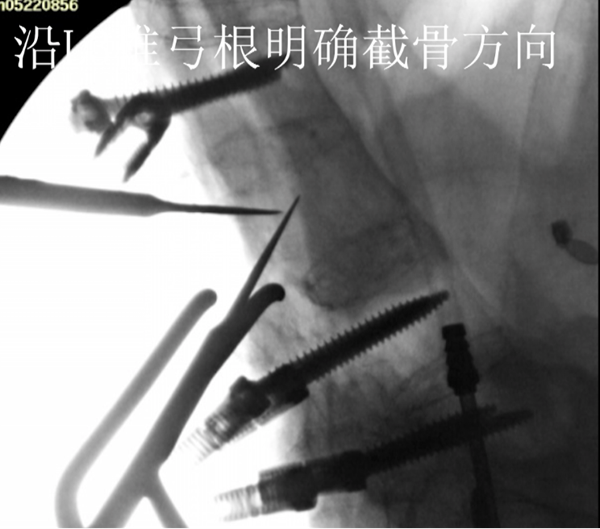

沿L1椎弓根明确截骨方向及角度

沿L3椎弓根明确截骨方向及角度